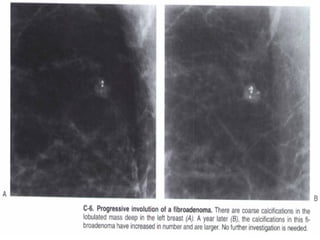

Typically benign

Skin, vascular, coarse, large rod like, round or punctate

(< 1mm), rim, dystrophic, milk of calcium and suture

calcifications are typically benign.

There is one exception of the rule: an isolated group of

punctuate calcifications that is new, increasing, linear,

or segmental in distribution, or adjacent to a known

cancer can be assigned as probably benign or

suspicious.